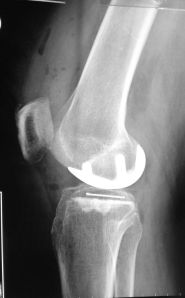

What Did I Do for this Patient?

This patient had severe pain and swelling of her right knee for about 3 months before consulting me. She is 56 years old.

She has tried pain killers, physiotherapy and use of crutches but her condition did not improve.

I performed a partial knee replacement for her.

Her pain improved significantly after the surgery and she was able to walk almost immediately.